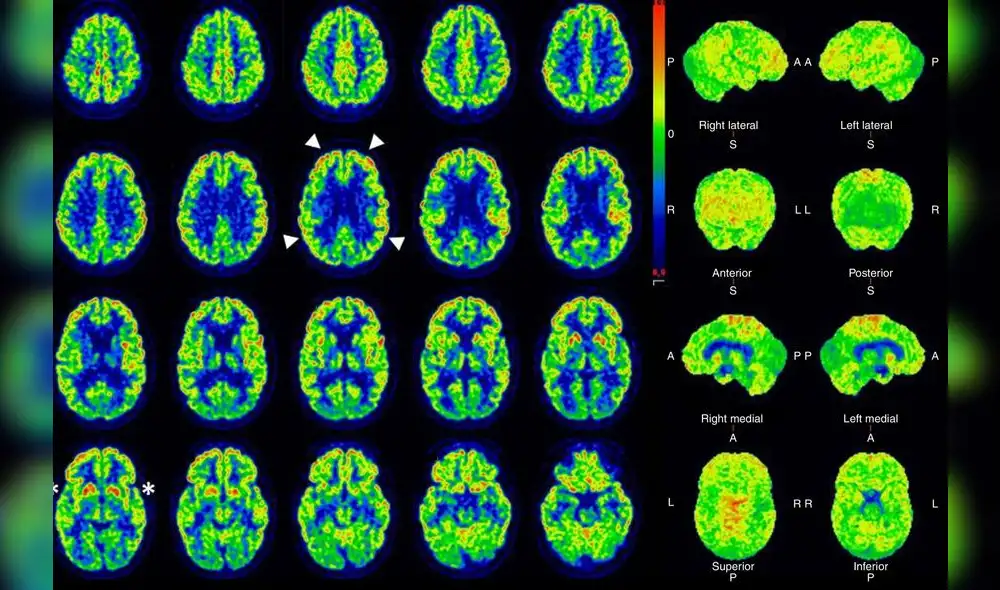

La "conciencia oculta" en los pacientes con lesiones cerebrales fue identificada mediante el uso de tecnología de resonancia magnética funcional (fMRI) y electroencefalograma (EEG). Estos métodos permitieron a los investigadores detectar actividad cerebral que indicaba respuestas cognitivas, a pesar de que los pacientes no mostraban signos externos de respuesta a órdenes.

En el estudio, se evaluaron a 241 participantes con lesiones cerebrales graves, utilizando resonancia magnética funcional, electroencefalograma o ambas técnicas, para detectar signos de actividad cognitiva no observada externamente.

Durante estos estudios, los participantes recibieron indicaciones como "imagine que abre y cierra la mano", seguidas 15 a 30 segundos después por "deje de imaginar que abre y cierra la mano". Los resultados obtenidos a través de resonancia magnética y electroencefalografía revelaron que 60 de los participantes (el 25 por ciento) siguieron estas instrucciones mentalmente de manera repetida durante varios minutos.